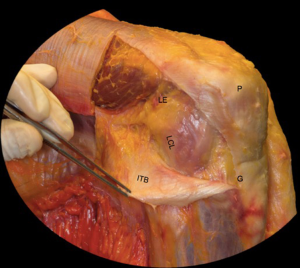

The symptomatology of LCL injury includes swelling, lateral joint line pain, difficulty ascending and descending stairs, and problems with cutting or pivoting. Patients classically ambulate with knee hyperextension or have a varus thrust gait. Lateral joint line tenderness also can occur and patients typically have opening with varus stress at 30 degrees of knee flexion. If there is varus instability at both 0 and 30 degrees, concomitant ACL and/or PCL injury is likely. If patients have increased tibial external rotation at 30 degrees, a combined LCL and PLC injury is probable. A careful neurovascular exam is important, as common peroneal nerve injuries can occur. Grading of the LCL as well as the PLC are quantified by the amount of lateral gapping with varus stress where grade I is defined at 0–5 mm opening, grade II is 5–10 mm, and grade III is >10 mm. Grade I and II indicate a partial tear, while grade III represents a complete tear. Radiographic analysis includes AP, lateral, and varus stress views while MRI is the imaging method of choice to provide information on the location and severity of the soft tissue injury (Figure 2) (7). Although posteromedial in anatomic location, interest in the posteromedial capsular attachment to the medial meniscus has grown, as a tear here, coined a ramp lesion, has been shown to possibly impart important rotational stability as well (Figure 3) (8). With injury to the PLC, meniscocapsular separation medially can occur and also should be investigated. Currently, no physical examination has been found to be sensitive or specific in diagnosing ramp lesions.

Surgery is indicated in grade III injuries, patients with rotatory instability (indicating both an LCL and PLC), and posterolateral instability (indicating LCL/PLC and ACL/PCL injuries). Controversy exists and it is not agreed upon in regard to the best repair and reconstruction sequence of these complex injuries. Improved outcomes result with acute surgery, as long as the soft tissue envelope allows. Successful outcomes have been show if surgery is done within 2 weeks, using suture anchors for avulsion injuries and suture repair alone for those of the midsubstance. In isolated LCL reconstruction, patellar tendon autograft has resulted in good outcomes. In LCL with popliteofibular ligament reconstruction, figure of eight Larson technique is utilized where a hamstring graft is passed through a fibular head bone tunnel which is consequently anchored to the lateral femoral anatomic origin. Another option is the transtibial double-bundle technique. Here, an allograft of the Achilles tendon is fixed to the femoral anatomic origin, and then tendon is split with half then being secured to the fibular head through a bone tunnel, while the other half is attached to the posterior tibia. A thorough physical exam is crucial for prompt diagnosis of complex lesions as this likely improves outcomes (10). Again, knee instability secondary to the improper healing of these injuries are likely to be pain generators and may lead to rotatory instability. The more recent identification of ramp lesions and their possibly role in knee stability has led some to advocate for fixation of these with the possibility that neglect of these lesions may be a cause of failure of ligament reconstruction and continued pain (Figure 3) (8).